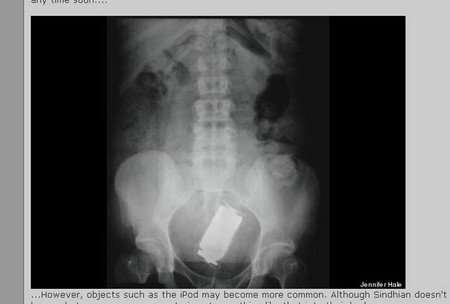

Có một cô gái muốn nghe nhạc từ bụng, nên cô nhét cả chiếc ipod vào đây.